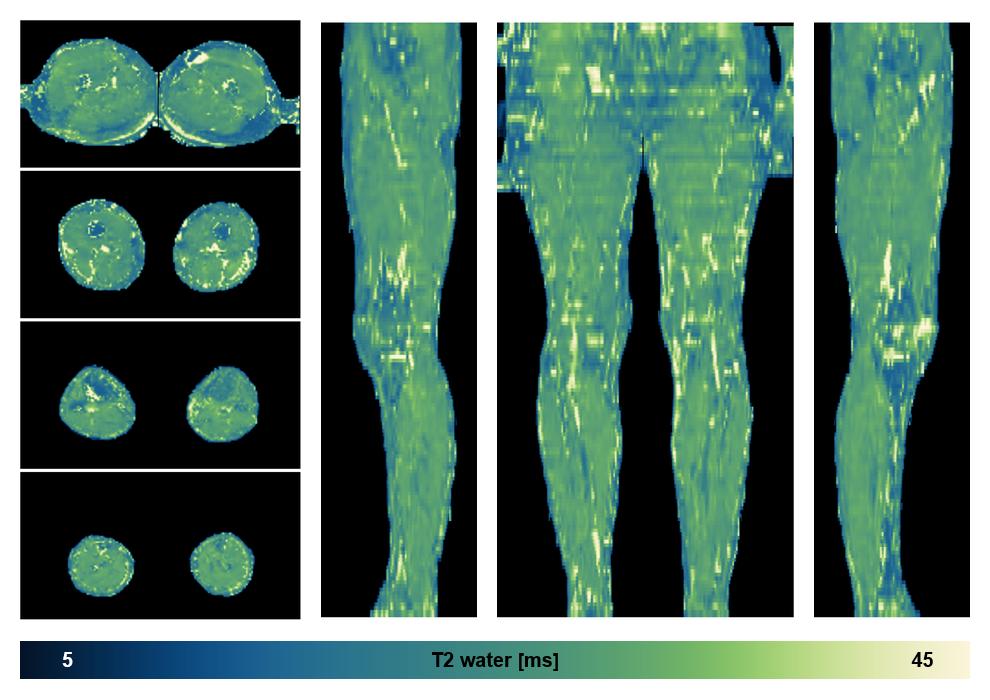

Water only T2 mapping

Multi echo spin echo T2 relaxation time mapping with EPG reconstruction, for information look here».

• Water only signal

The water part of the acquired multi-echo spin echo data.

• Water only T2 relaxation time

The water only T2 relaxation time of the lower extremity obtained from multi echo spin echo t2 mapping with EPG based reconstruction.